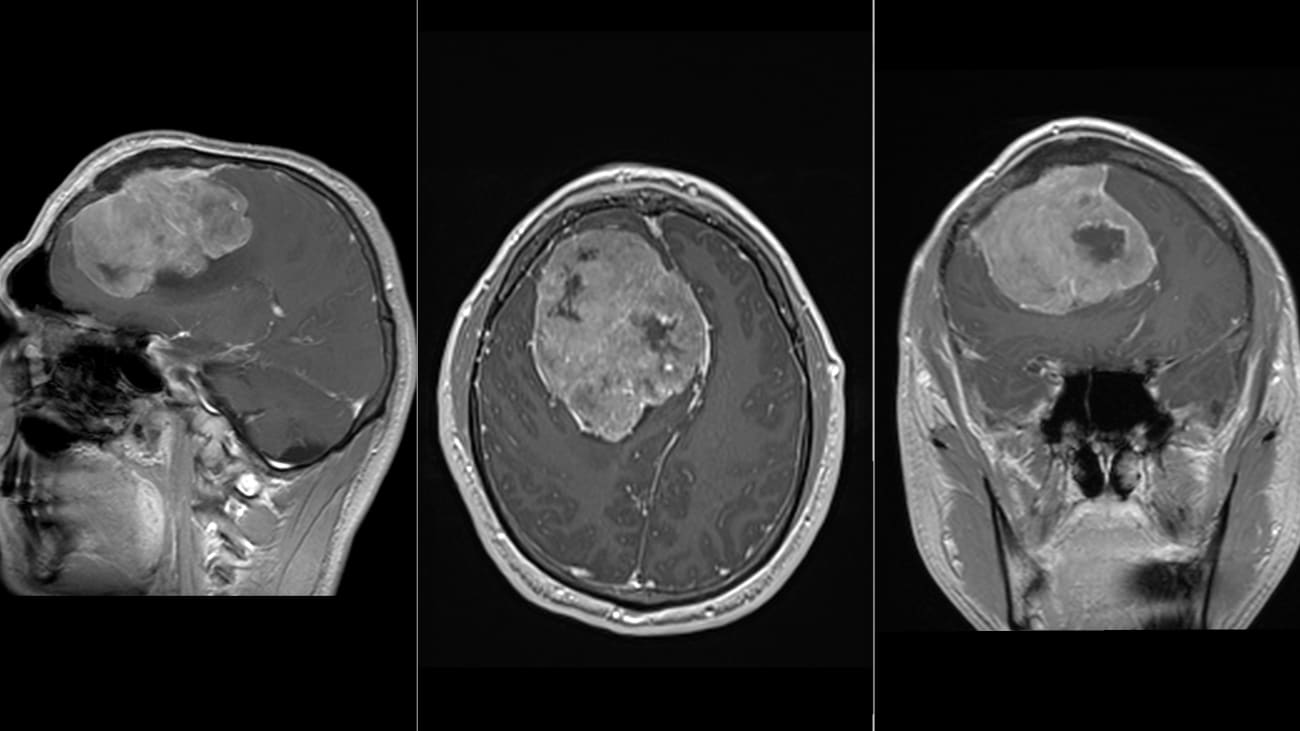

Postoperative scan after resection of a giant meningioma, showing the surgical result and successful tumor removal, and restoration of intracranial space.

Following successful resection, the patient experienced meaningful improvement in the symptoms driving functional decline. Over time, he was able to resume higher levels of activity and return to the routines and relationships most important to him - reflecting the core objective of modern neurosurgery: not simply removing a tumor, but protecting independence and restoring quality of life.